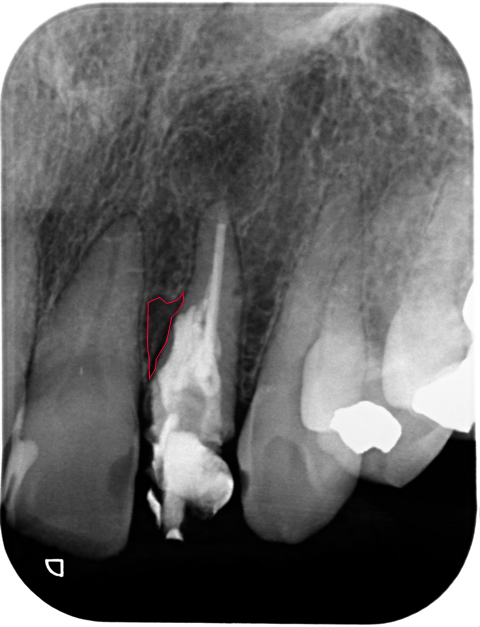

この症例の16ヶ月経過です。

赤い線で囲まれた部分が病変です。原因はパーフォレーション。

歯根破折の心配は消えませんが、病変はほぼ消えてlamina dura(歯槽硬線)も現れてきています。良好な経過を患者さんに伝えることができた時は晴れやかな気持ちになります。